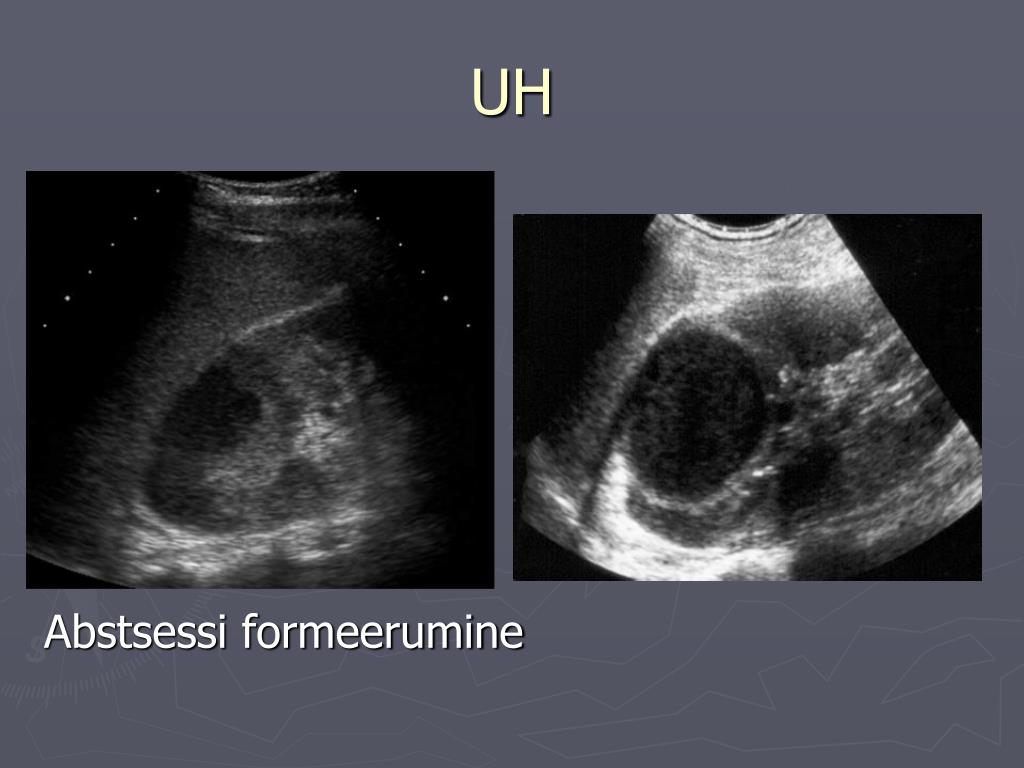

8. UH 25% UH-uuringutel on positiivne tulemus. • neerude suurenemine • ebaühtlase ehhogeensusega • siinuse ehhogeensuse langus (ödeem) • kortikomedullaane diferents on langenud • abstsessi moodustumine

18. UH Abstsessi formeerumine